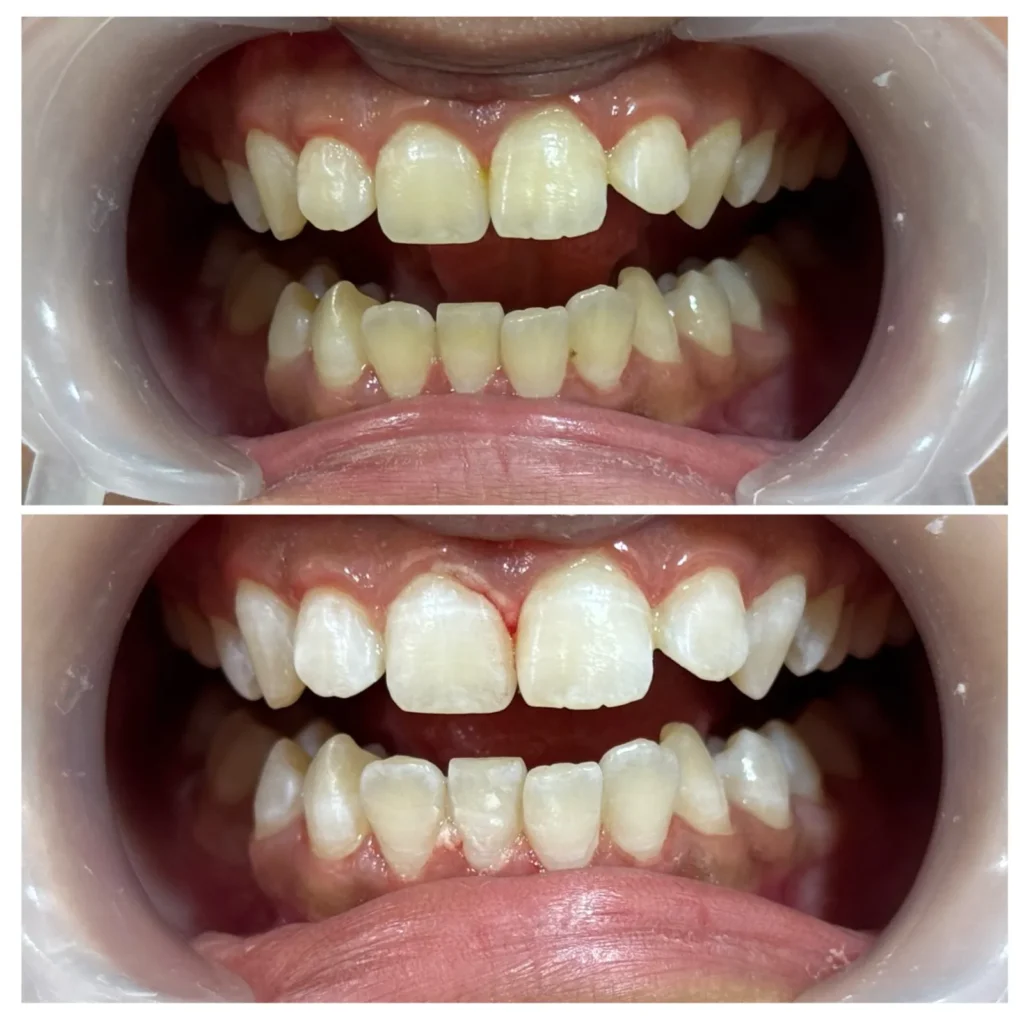

Our Dental Results we’ve delivered

Teeth Cleaning & Whitening